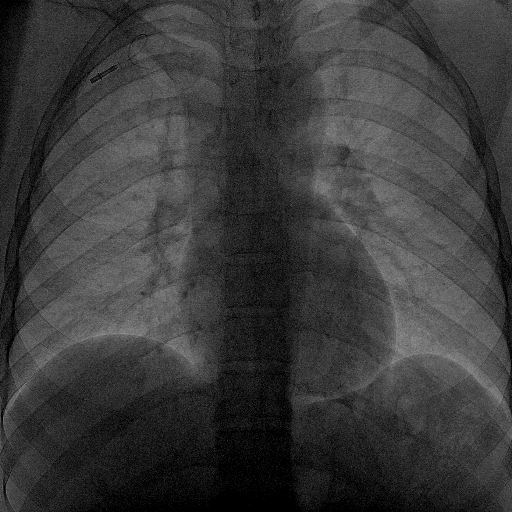

A twenty nine years old lady diagnosed as Carcinoma left breast underwent breast conservation surgery (pT2N2aM0, ER positive PR positive Her 2 neu positive) and presented for adjuvant chemotherapy. She was planned for adjuvant chemotherapy, radiotherapy and hormonal therapy as per standard guidelines. Chemoport reservoir was placed in the chest wall – right infraclavicular fossa and chemoport catheter was placed in the right subclavian vein. Post-procedure chest x ray revealed proper placement of the chemoport. She underwent first cycle of adjuvant chemotherapy with Docetaxel, Carboplatin and Trastuzumab without any complications. When she presented for second cycle (45 days after chemoport insertion), she was asymptomatic. However, there was no backflow of blood from the chemoport reservoir. Chest X ray revealed fragmentation and embolization of chemoport catheter. ECG showed normal sinus rhythm. Non Contrast CT scan chest was done, which revealed that the distal fragment of chemoport catheter had embolized to left pulmonary artery lower lobar branch, having migrated across the right atrium, right ventricle, main pulmonary artery and its left branch (Figure 1). After informed consent, retrieval of distal fragment of chemoport catheter was done in cath lab under local anesthesia under fluoroscopic guidance by Interventional Radiology team. It was retrieved from left pulmonary artery lower lobar branch in a procedure lasting forty minutes. The right femoral vein was punctured, 10 Fr Cordis sheath was introduced into the femoral vein, left pulmonary artery was cannulated using cobra 5 Fr catheter and then it was exchanged with snare over the guide wire. The left posterior inferior branch of pulmonary artery was selectively cannulated using Terumo guide wire and Cobra catheter. The tip of the foreign body was snared using Sequre snare system (4Fr, 10mm) and pulled through the pulmonary artery (Figure 2). The length of the catheter fragment was 4cm (Figure 3-9). The next day, chemoport reservoir and the proximal fragment of chemoport catheter was retrieved by surgery under local anesthesia. Patient tolerated both procedures well and was discharged on the third day.

Figure 8 Check fluoroscopy image after removal of foreign body.